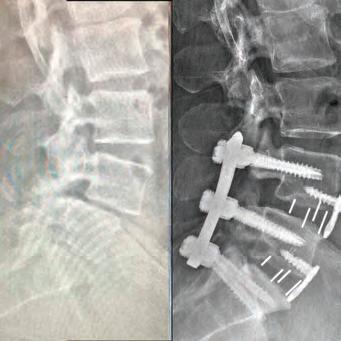

Led by Dr. Courtney, the skilled team at Advanced Spine Center cares for patients with neck and back pain using a wide array of the most state-of-the-art tools and techniques—from conservative physical therapy and injection therapy—to advanced pain manage-

SPINE SURGEON PRACTICING FOR 28 YEARS.

ment, as well as surgical intervention. We employ the latest in minimally invasive spine surgeries, in addition to cutting-edge replacement technology. Incorporating both high tech and high touch, we get our valued patients back to their lives so they can enjoy all the activities they love.

SURGERY: L5/S1 360° LUMBAR FUSION

SURGERY: L4/5, L5/S1 360° LUMBAR FUSION